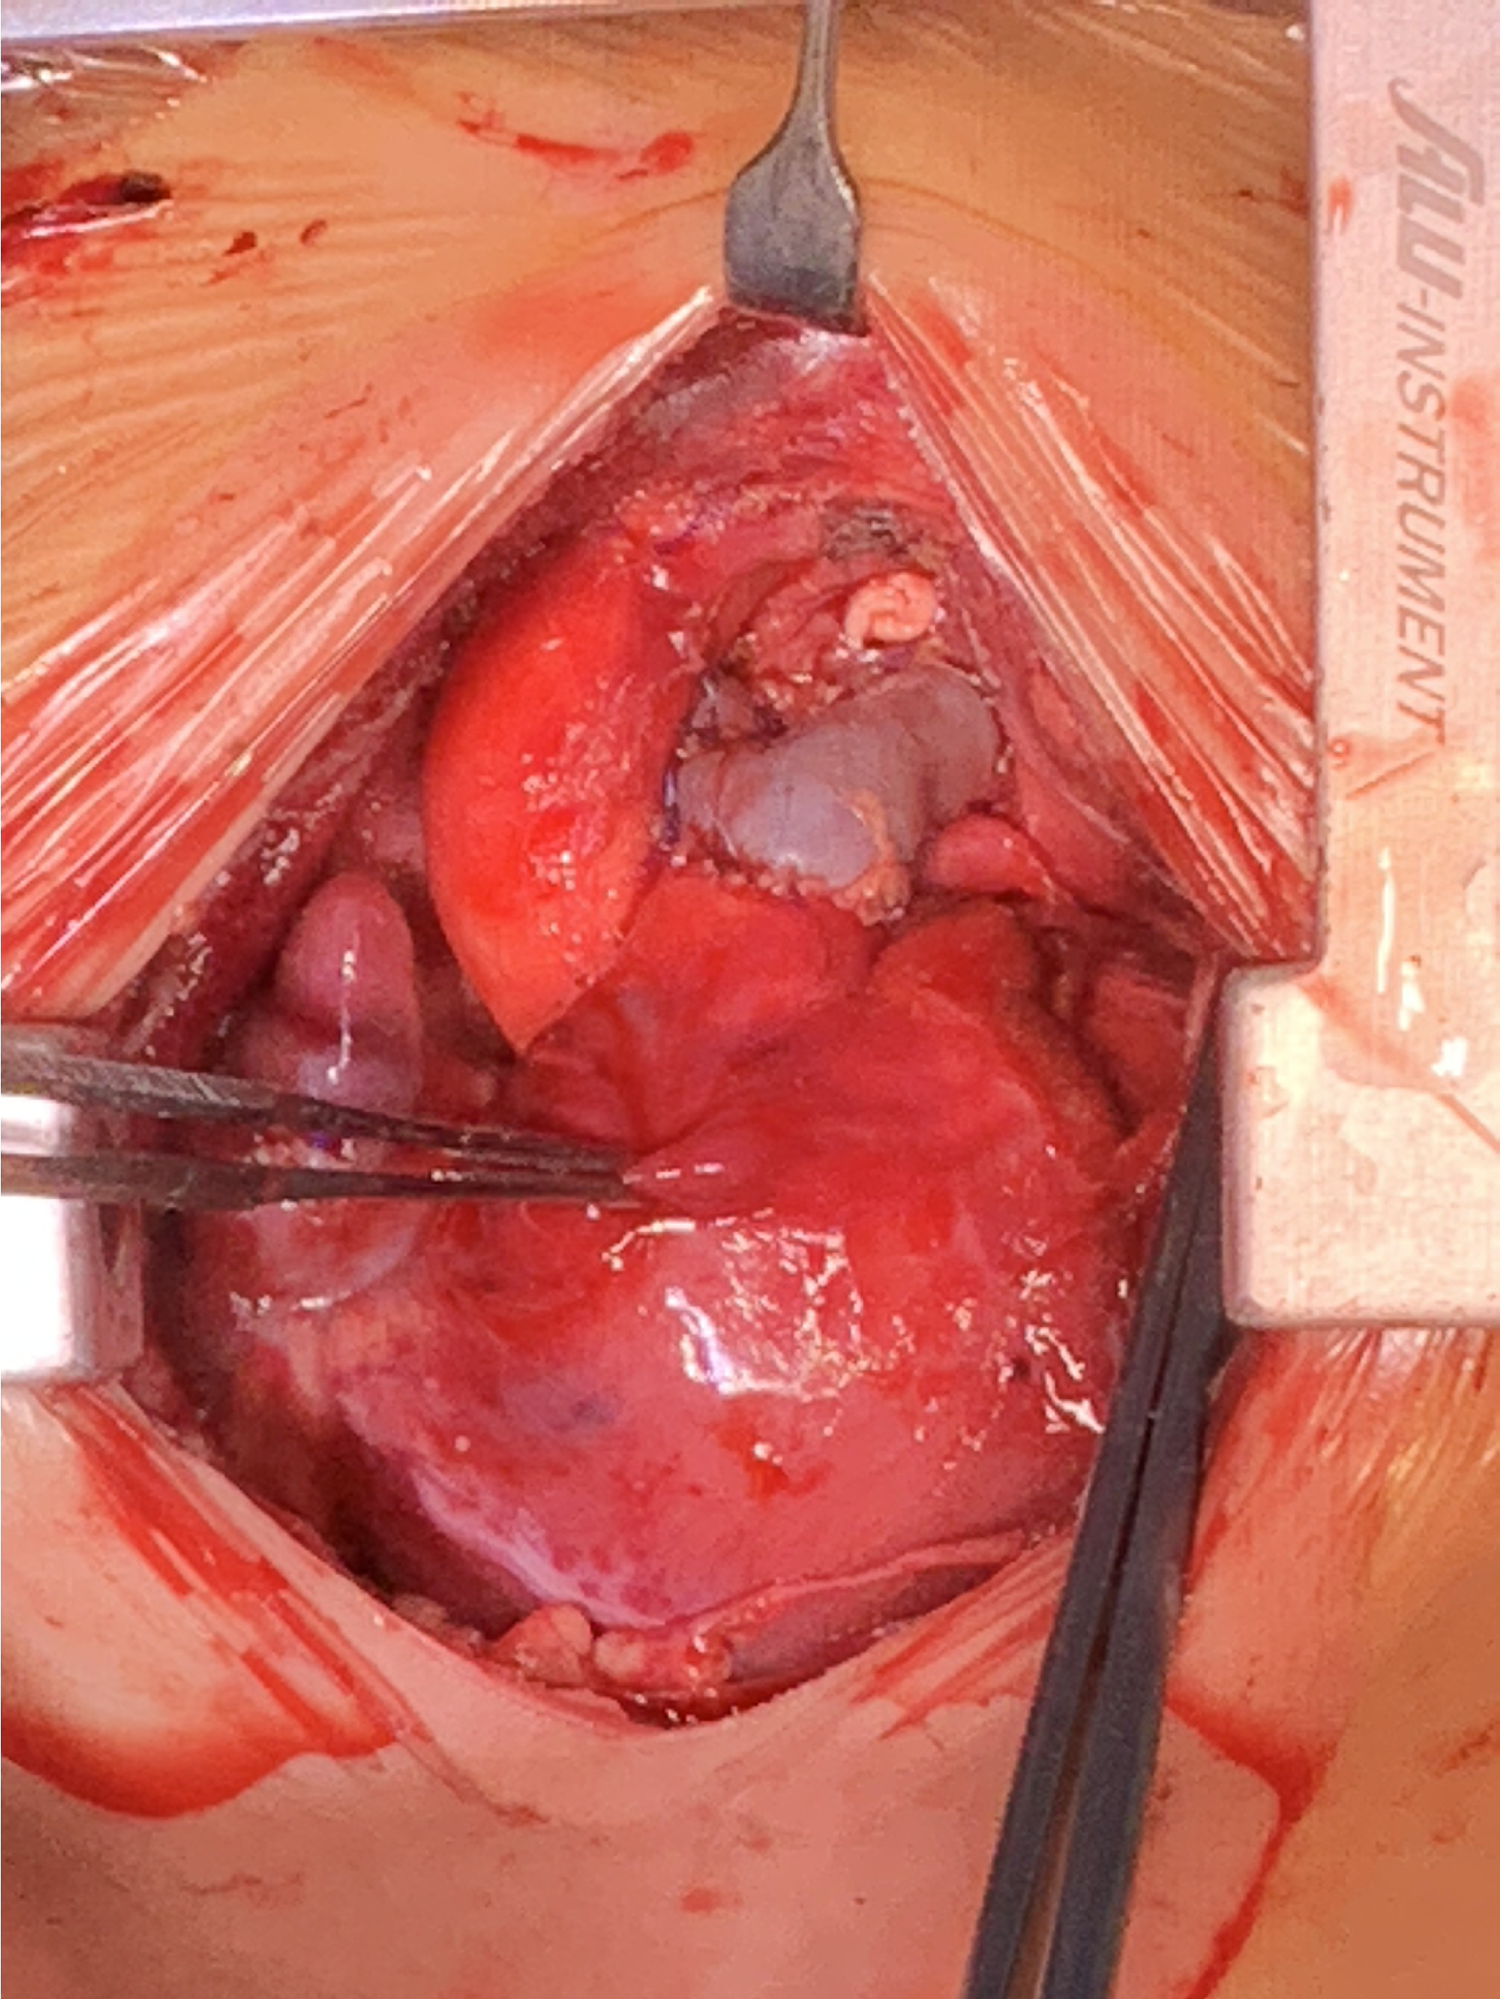

After careful evaluation, the diagnosis of UAPA was confirmed, and the operation was electively performed on the patient. After median sternotomy, the pericardium was harvested and treated with glutaraldehyde solution for five minutes. The origin of the right ductus was visualized after the innominate artery mobilization. The distal RPA was located posterior and medial to the SVC. Bilateral branch PAs were completely dissected beyond the lobar division to facilitate a tension-free PA anastomosis. The AAo was also mobilized sufficiently to create adequate space for the neo-RPA. Cardiopulmonary bypass was established via AAo and bicaval cannulation. The operation was performed under mild hypothermia (34°C) with a beating heart. After transecting the left ductus, an extension flap was created using the anterior wall of MPA and LPA with the base of the flap located along the right lateral aspect of the MPA and slightly inferior to the level of the proximal LPA (Figure 2A). Care was taken to leave a 5 mm margin of MPA tissue above the sinotubular junction to preserve pulmonary valve function. The distal incision for the extension flap terminated just proximal to the LPA hilum (Figures 2B; 3A). The RPA was then harvested and ductal tissue was completely resected. The RPA was controlled distally with vessel loops on the lobar branches. Exposure was obtained by retracting the vessel loops distally. An incision was made along the inferior aspect of the right lower lobar branch to enlarge the RPA hilum (Figures 2C, 3B). The PA flap was then sutured to the distal segment of the opened RPA to construct the posterior aspect of the neo-RPA using running 7-0 polypropylene sutures (Prolene, Ethicon Inc, USA) (Figure 2C). The inferior, anterior, and superior aspects of the neo-RPA were reconstructed using a glutaraldehyde-treated autologous pericardial patch with a tongue extending into the right lower lobe according to the orientation of the vessel (Figures 2D, 3C). Running 8-0 polypropylene sutures were used for this portion of the PA angioplasty. After completion of the RPA reconstruction, the anterior wall of MPA and LPA was reconstructed with a second treated autologous pericardial patch (Figures 2E, 3D. After finishing the procedure, we successfully reconstructed the PA with satisfactory morphology and diameters (Figure 4). The patient recovered from the surgery uneventfully. Postoperative echocardiography demonstrated no residual vascular shunt and laminar flow in RPA. Postoperative CTA after 1 month revealed normal PA branching patterns and diameter. The patient remains asymptomatic and well upon last follow-up.

Figure 3

Intraoperative pictures of modified pulmonary artery flap angioplasty corresponding to procedure diagram. (LPA, left pulmonary artery; MPA, main pulmonary artery; RPA, right pulmonary artery.